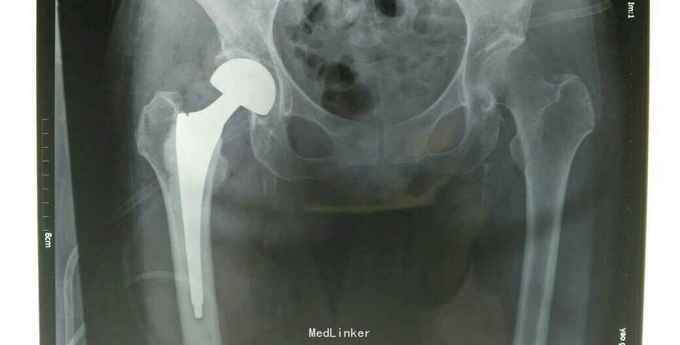

右股骨颈骨折 完善相关检查后行右股骨颈骨折股骨头置换术。

术后一个月,门诊复查